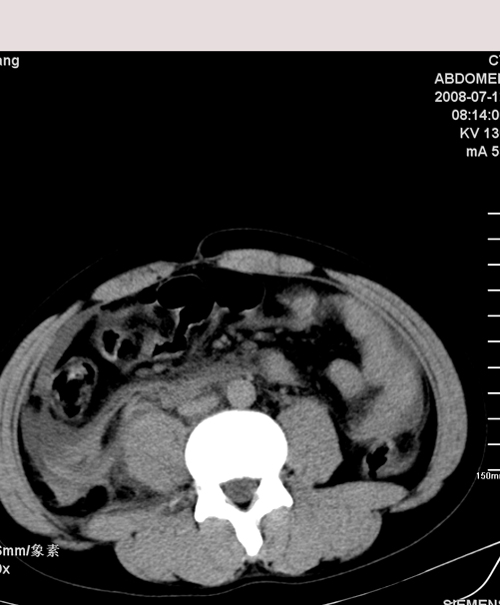

以下是引用muzi888在2008-7-15 10:45:00的发言:[br]大量腹腔积液,气腹,肾皮质弧形高密度影,诊断;1 空腔脏器穿孔 2 右肾包膜下血肿

以下是引用随光逐影在2008-7-15 11:18:00的发言:[br]考虑为:1)腹部空腔脏器穿孔。2)右肾破裂并肾包膜下血肿,肾盂积血。3)腹水(血)。